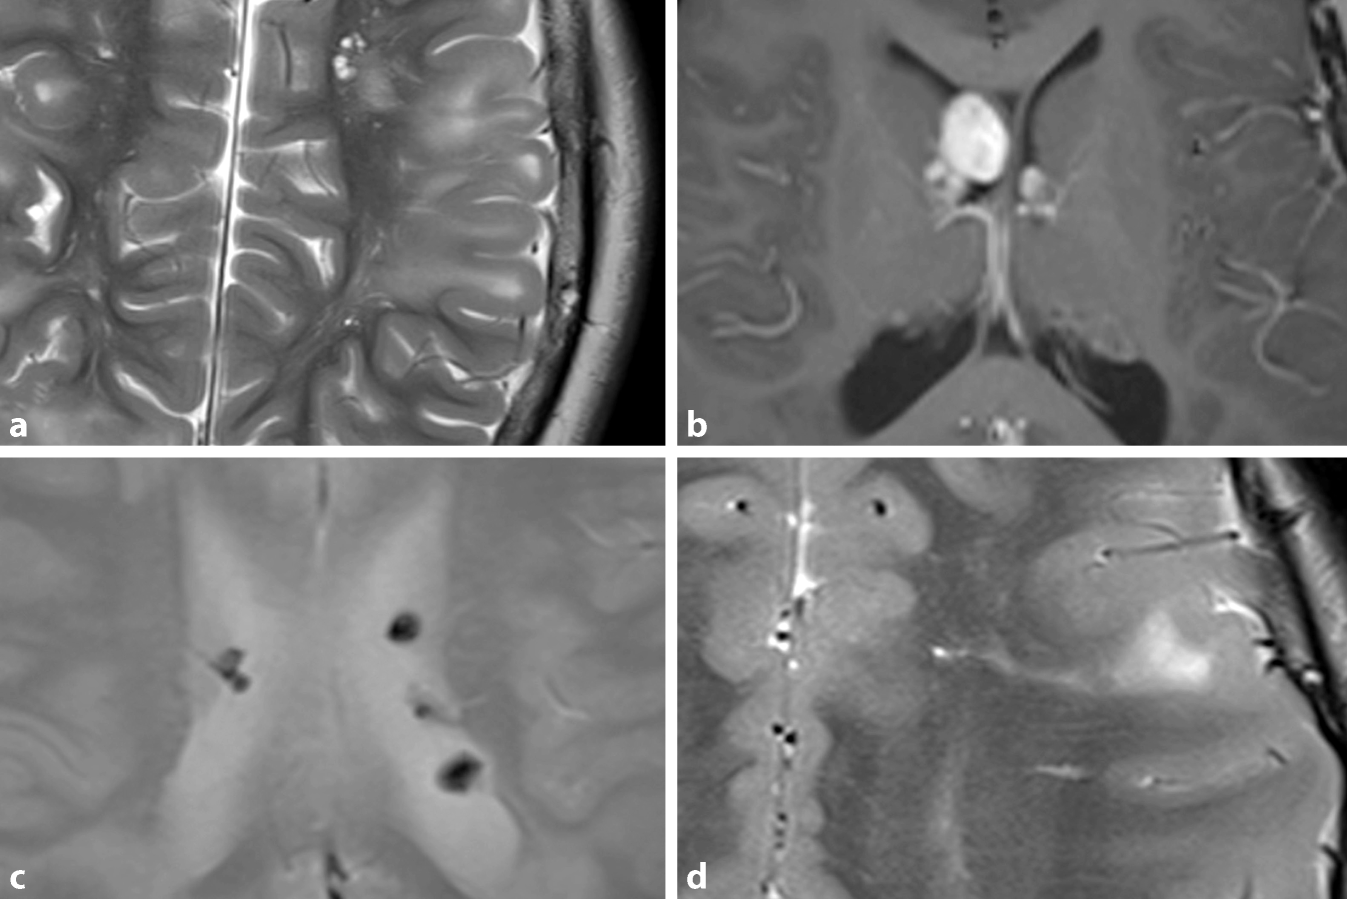

Neuroradiologie Wie Behandelbare Formen Der Demenz Erkannt Werden

Zns Manifestationen Der Phakomatosen Springerlink